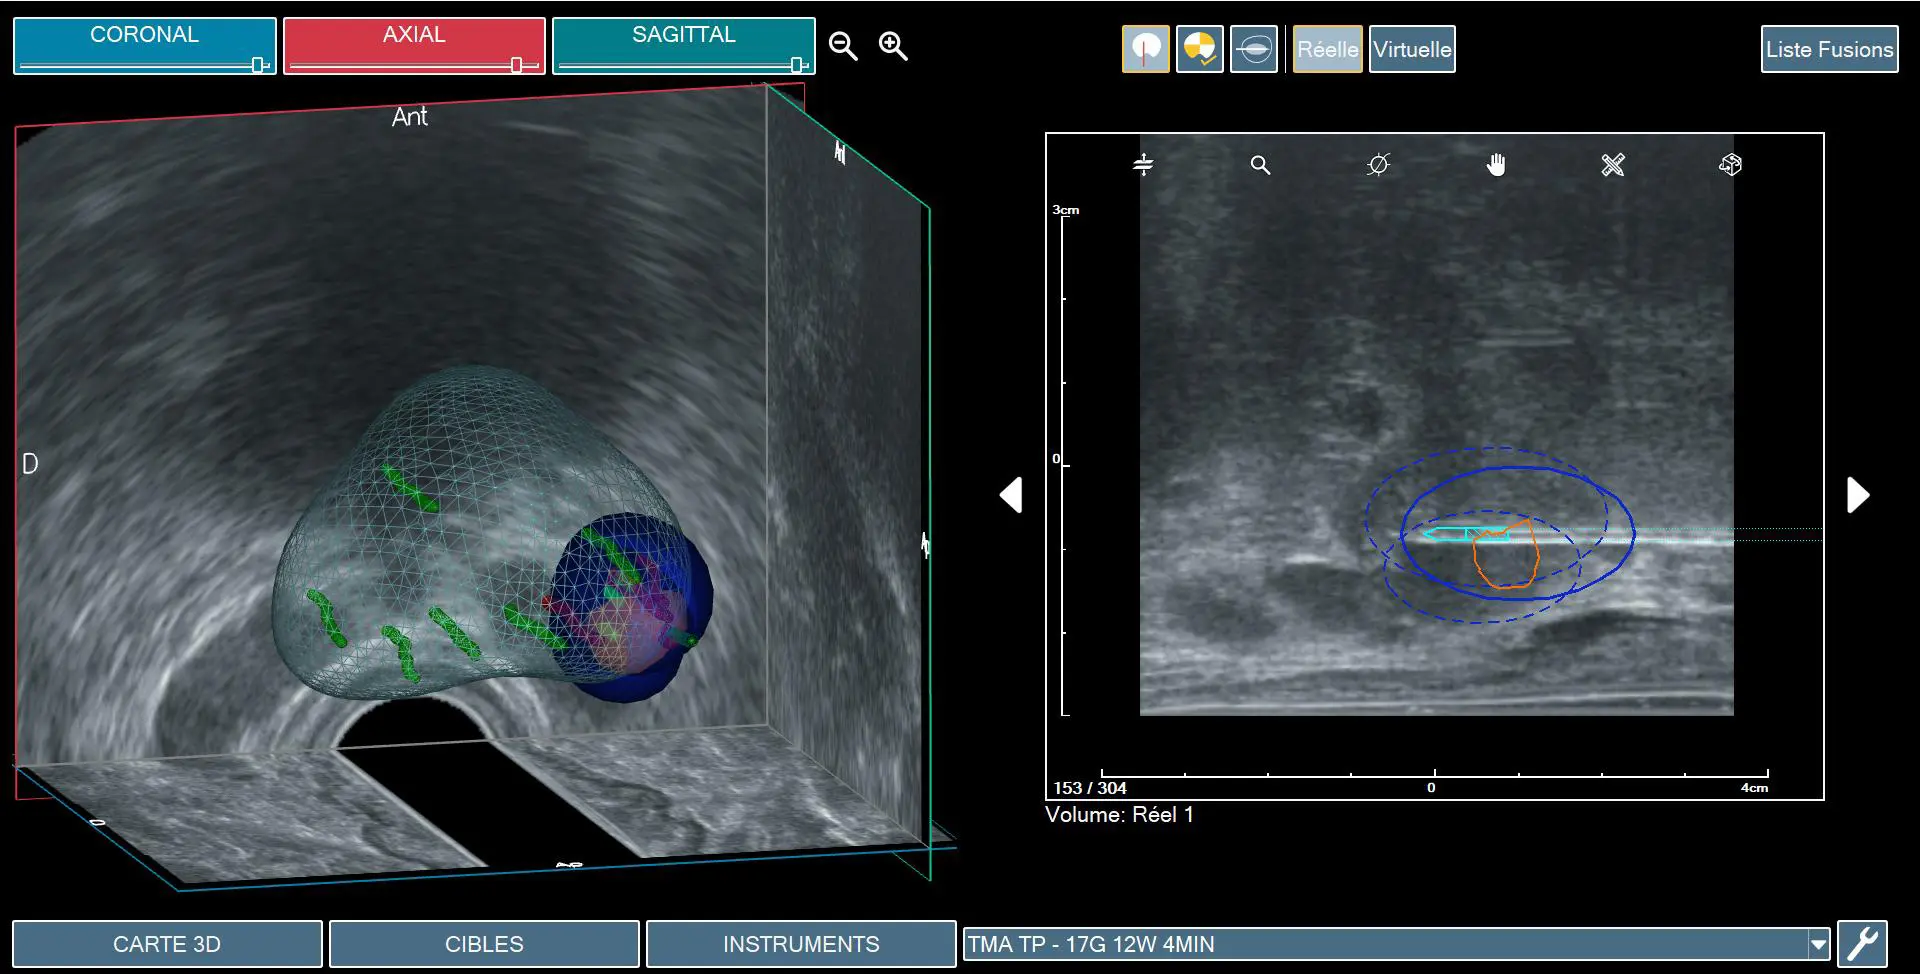

Rekonstrukcja bryły prostaty do leczenia TMA ogniska raka w lewym płacie

Zastosowanie marginesów leczenia TMA na tle biopsji fuzyjnej

TMA (Targeted Microwave Ablation) to mikrofalowa terapia celowana, w której wykorzystywane są te same modele wirtualne prostaty, jakie stosujemy w biopsji fuzyjnej. W praktyce oznacza to, że lekarz trafia dokładnie w ten sam punkt, z którego wcześniej pobierał wycinek do postawienia diagnozy — tyle że zamiast pobierać próbkę, wprowadza igłę emitującą mikrofale. W taki, wysoce precyzyjny sposób przy wykorzystaniu TMA, niszczone są komórki nowotworowe.

• TMA opiera się na danych z rezonansu magnetycznego, który był wykonany wcześniej i pod kontrolą nawigacji przestrzennej jest w stanie trafić w ściśle określony nieduży punkt tzn. ognisko raka w prostacie. Dzięki temu oddziaływanie jest tylko na to konkretne miejsce, które stanowić może zaledwie kilka procent całej prostaty, ale w którym znajduje się rak istotny klinicznie.